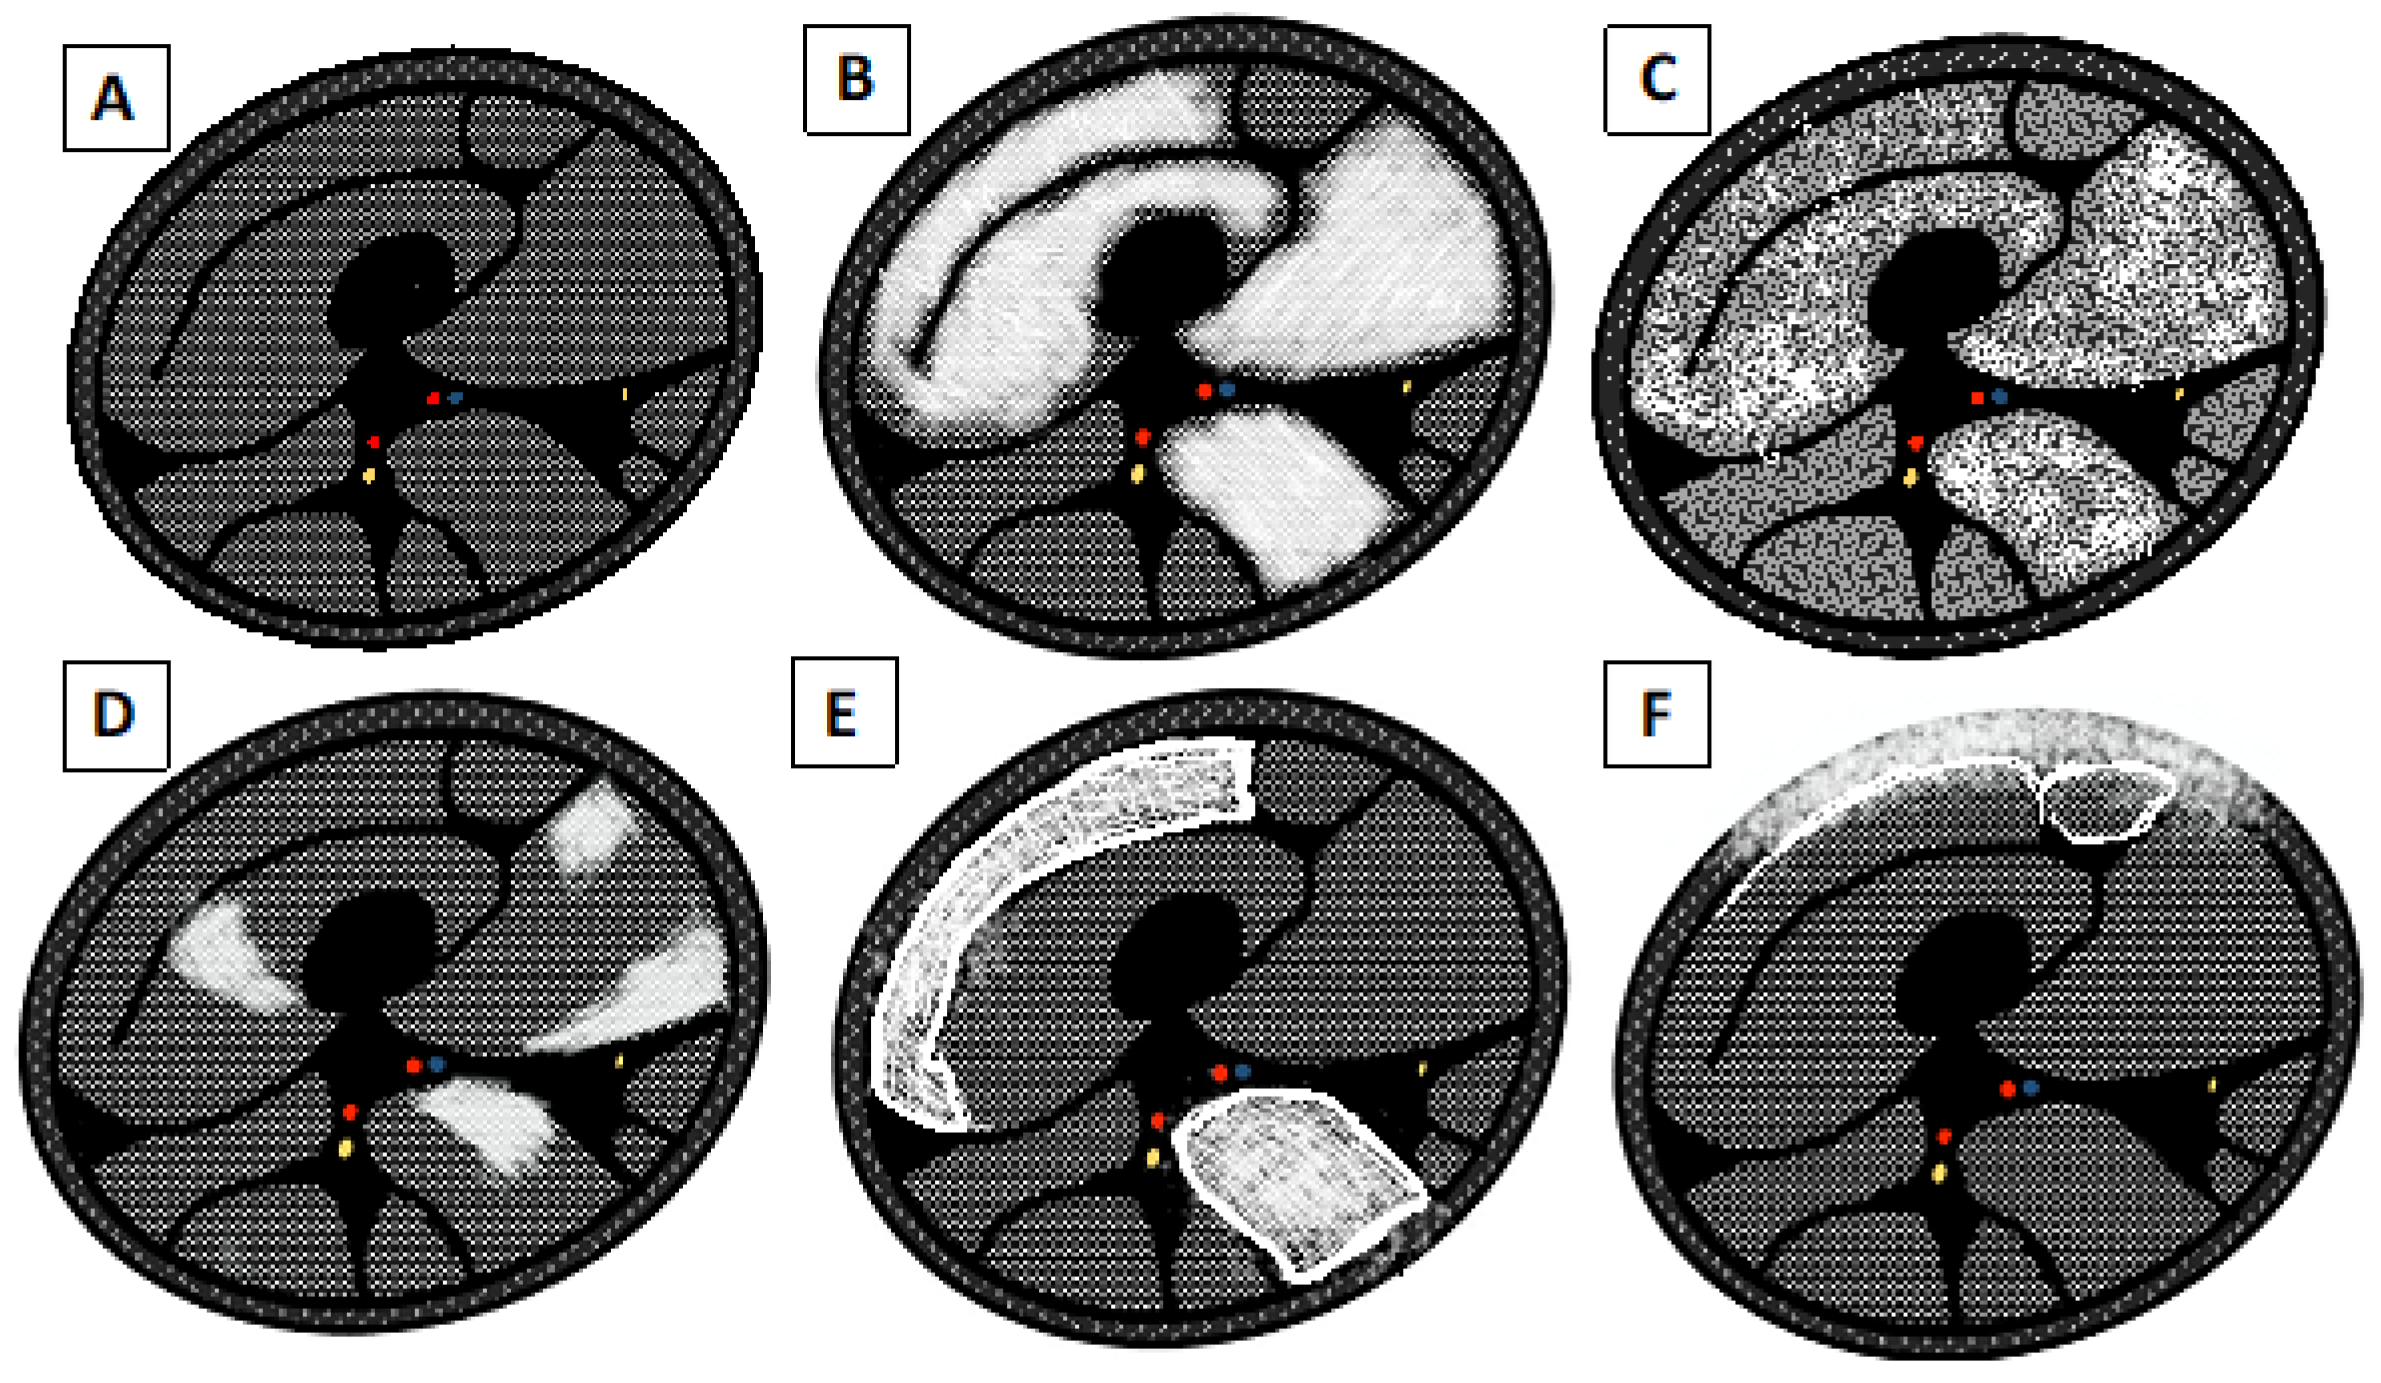

3.1. Distinction between Active and Chronic Disease

3.1.1. Acute Changes

3.1.2. Chronic Changes

- 0 = Normal intensity appearance of the muscle.

- 1 = Early moth-eaten appearance with scattered small areas of high intensity on T1-weighted imaging.

- 2a = Late moth-eaten appearance, with numerous areas of high intensity on T1-weighted imaging, with beginning confluence comprising less than 30%.

- 2b = Late moth-eaten appearance, with numerous areas of high intensity on T1-weighted imaging, with beginning confluence comprising 30–60%.

- 3 = Washed-out, fuzzy appearance due to confluent areas of increased intensity in T1-weighted imaging, with muscle still present at the periphery.

- 4 = End-stage appearance; all muscle replaced by fat with high intensity in T1-weighted.